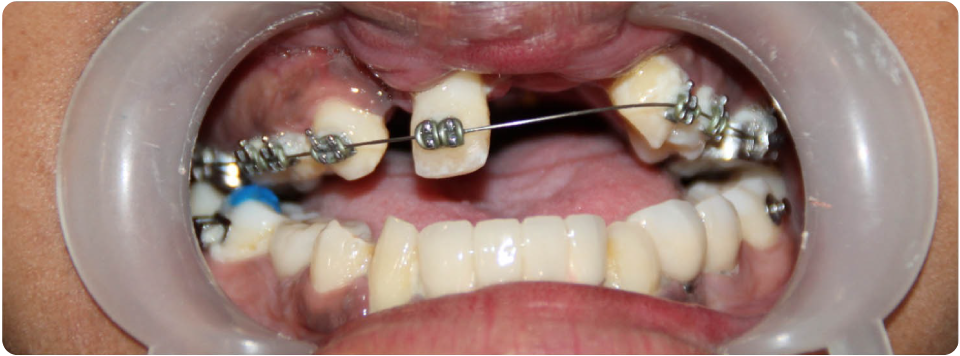

3D Guided Implant Surgery

After 3D imaging the implant is placed virtually in a software and a 3D guide is fabricated.

Essentially, this guide is placed inside of your mouth at the time of your implant surgery and the implant placement is done through the guide. This guide insures exact position depth and angulation of the implant increasing the success rate of the procedure.

Advantages – painless, shorter surgery time, faster recovery, less invasive, 100% accuracy.